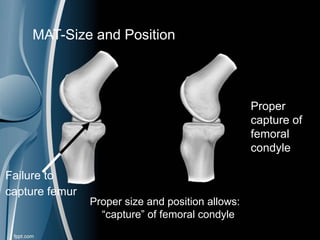

MAT-Bone Bridge

Failure to

capture femur

Proper

capture of

femoral

condyle

Proper size and position allows:

“capture” of femoral condyle

MAT-Size and Position